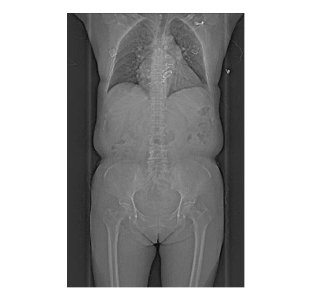

支持“無禁忌”全身檢查,尤其適合急癥患者(如急性胸痛、胸痛三聯(lián)征)的“一站式”快速檢查,為搶救贏得黃金時(shí)間。

1.心腦血管疾?。?.14秒完成心臟掃描,冠脈成像不受心率限制,也同時(shí)支持心肌灌注評估。 2.腫瘤診療:雙能量技術(shù)助力良惡性鑒別、療效監(jiān)測,實(shí)現(xiàn)腫瘤體積、密度的動態(tài)追蹤。3.神經(jīng)系統(tǒng)檢查:對于腦外傷、出血、腫瘤等疾病的診斷,可提供高質(zhì)量的圖像,幫助醫(yī)生準(zhǔn)確判斷病情。雙能量活動性腦出血分析和神經(jīng)灌注檢查,有助于評估腦卒中缺血半暗帶,為臨床治療決策提供重要參考。 4.急診與重癥:1秒全身成像快速排查多發(fā)傷、肺栓塞等急危重癥,縮短檢查時(shí)間。

檢查無需藥物控制心率或長時(shí)間準(zhǔn)備,減少等待焦慮。80cm超大掃描范圍,肥胖或特殊體位患者亦可輕松完成檢查。